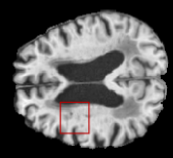

We evaluated our method in segmenting WMH from T1-w images using: a) Synthesized FLAIR images by treating the synthesis as a preprocessing step – we will refer to this method as offline synthesis; b) Synthesized FLAIR images using the proposed method, and c) without any synthesis – we will refer to this method as Unimodal. Baseline methods are illustrated in Figure 2

Table 2: Segmentation results for all proposed methods, each column represent a different slide in the image, blue areas are regions which were correctly labeled, false positives are shown in green, and false negatives in yellow

In order to better understand the above results, we visually analyzed the output segmentation performed for each method. Table 2 shows the results for three different slices (one slice per column). As illustrated, the proposed method is able to produce less false positives. It is also important to note that, unimodal segmentation is the one that produces more false positives, showing the advantage of using synthetic data. Regarding the nature of false positives, it can be easy to see in the third column a large number of false positives are on the border of periventricular lesions for the Unimodal method in comparison to the proposed method. Also from the first and second column, it can be observed that Unimodal tend to produce more small regions of false positives near to cortical areas. Removing such false positives requires additional post-processing steps, therefore, it is of value avoid this kind of over-segmentation. It can also be noted that synthesis methods tend to produce the same kind of false negatives, this may be due to the blurring effects in synthesized images since the information available during testing is limited – which otherwise is available from a FLAIR sequence.